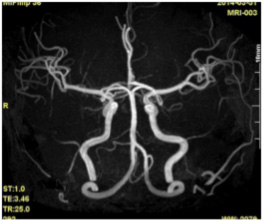

頭部MRI検査では頭蓋内の断面を、MRA検査では血管のみを抽出して立体的に画像化します。自覚症状が全くない初期の脳梗塞、いわゆる「隠れ脳梗塞」や、くも膜下出血の原因となる「脳動脈瘤」が早期発見でき、予防することができます。